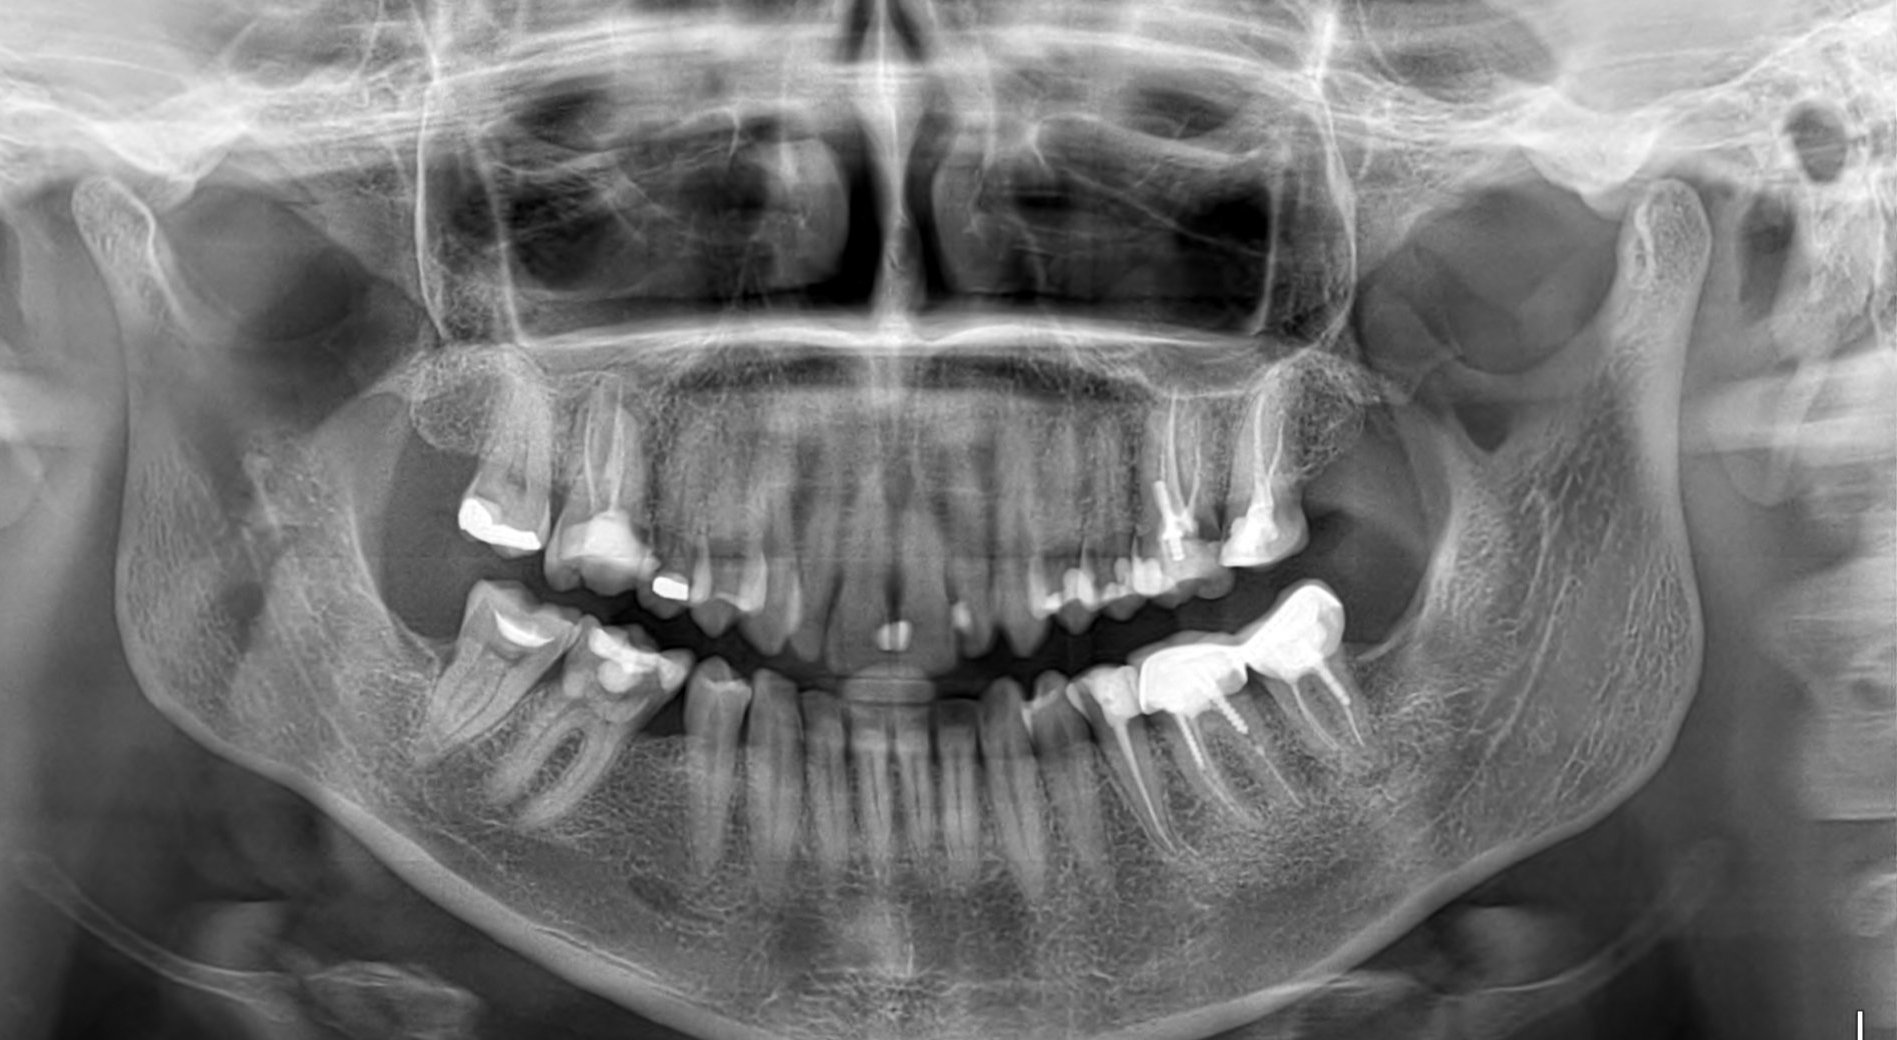

Здравейте! Аз свикнах да си пиша и никой да не ми отговаря, ама карай.. Днес ми се наложи да отида на зъболекар. Оказа се, че имам кариес под нивото на венеца, вижда се на снимката, вляво е. Стоматоложката каза, че трябва да се прелекуват добре двата зъба и да се направи една обща коронка. Притеснението ми е, че като го отвори, зъбът много миришеше. Работи ме около 3ч и половина. За това време може ли адекватно да се прелекува, дезинфекцира и каквото е необходимо там да се направи?През цялото време се притеснявах да не ми се перфорират каналите и в момента усещам нещо като леко тръпнене на венеца. Това нормално ли е? Утре ще направя панорамна снимка. От нея може ли да се види добре дали каналите са запълнени както трябва? Как да съм сигурна, че лекарката си е свършила добре работата?

На панорамната снимка няма да видите нищо за запълването на каналите. Трябва малка сегментна, но само ако вече е запълнила каналите окончателно.